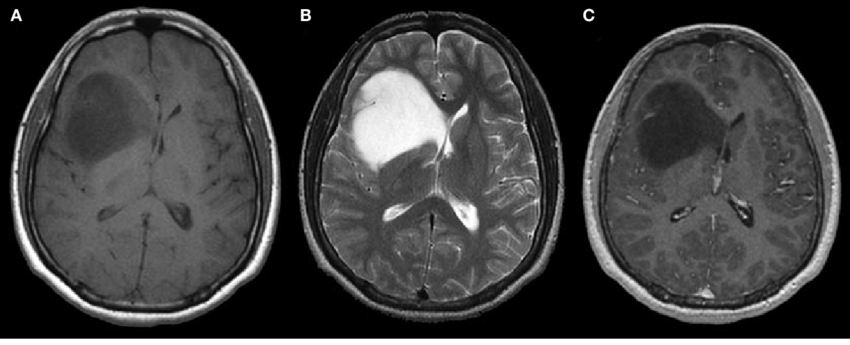

脑胶质瘤的分类是复杂的,部分基于肿瘤的微观外观(组织学分类),部分基于与肿瘤发展有关的基因变化(突变)。分化是脑胶质瘤的组织学分类的重要概念,是指细胞的“化”。例如,大脑中的某些细胞可以显示神经元或神经胶质细胞的分化,而胚胎干细胞则未分化。脑胶质瘤的组织学分类取决于肿瘤细胞与不同类型的神经胶质细胞(如星形胶质细胞和室管膜细胞)的微观相似性,肿瘤的生长方式和行为以及肿瘤内细胞的分化程度(等级)。

脑胶质瘤可具有四种不同的分化等级。1级脑胶质瘤表现出较高的分化水平,恶性程度很低,而4级肿瘤则分化程度较低,恶性程度较高。分化的丧失被称为发育不良,因此是几种3级神经胶质瘤的名称。1级和2级脑胶质瘤通常被称为低度神经胶质瘤,而3级和4级被称为恶性脑胶质瘤。根据受影响细胞中发生的遗传改变,可进一步分类。

诸如术中磁共振(iMRI)之类的新技术可以允许神经外科医生获得更完整的切除。实现全切除的困难之一,特别是对于晚期的胶质母细胞瘤,MRI或神经外科医生不可见的微观肿瘤细胞可能超出明显的肿瘤边界。这是因为这些肿瘤是浸润性的,意味着是它们倾向于侵入正常的大脑结构。一些肿瘤细胞可能已经迁移到大脑的另一侧,与术前扫描和手术中看到的肿瘤相距很远。